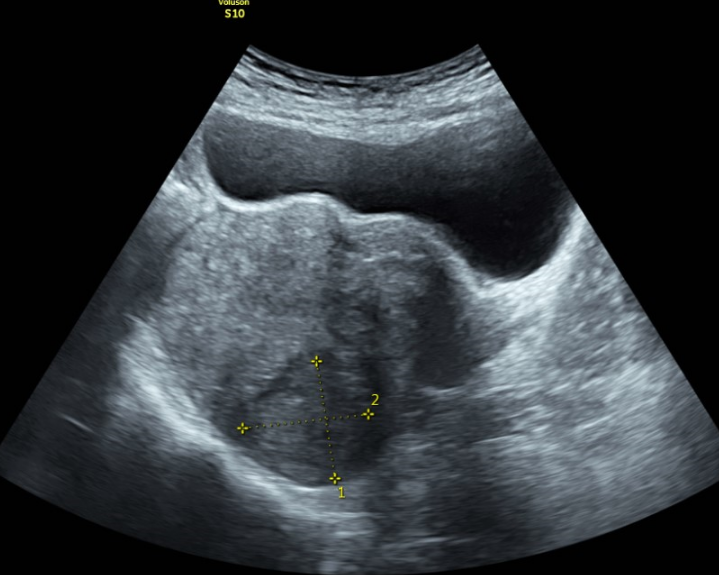

Siêu âm vùng chậu là phương pháp chẩn đoán hình ảnh không xâm lấn nhằm quan sát các cơ quan nằm trong vùng chậu. Thông thường bác sĩ có thể yêu cầu thực hiện kỹ thuật này để chẩn đoán tình trạng sức khỏe vùng chậu hoặc kiểm tra thai khi còn trong bụng mẹ. Vậy siêu âm vùng chậu là gì?

Siêu âm vùng chậu là kỹ thuật được áp dụng phổ biến nhằm mang đến những hình ảnh về các cơ quan và cấu trúc vùng chậu. Nếu đối tượng siêu âm là phụ nữ thì vùng chậu cần kiểm tra bao gồm âm đạo, tử cung, cổ tử cung, ống dẫn trứng và buồng trứng. Với nam giới, kỹ thuật siêu âm này giúp kiểm tra, chẩn đoán các vấn đề liên quan đến túi tinh, tuyến tiền liệt và bàng quang.

Siêu âm vùng chậu hay còn gọi là siêu âm vùng bụng dưới, siêu âm qua ổ bụng, siêu âm phụ khoa, siêu âm qua âm đạo… là một kỹ thuật chẩn đoán hình ảnh không xâm lấn nhằm tạo ra hình ảnh để bác sĩ đánh giá các cơ quan và cấu trúc bên trong khung chậu.

Kỹ thuật siêu âm này sử dụng đầu dò truyền sóng âm ở tần số cao thường áp dụng khi siêu âm thai kỳ. Sóng siêu âm từ đầu dò dội vào các cơ quan và mô trong cơ thể, sau đó dội ngược trở lại đầu dò. Sóng âm truyền đến máy tính chuyển đổi thành hình ảnh các cơ quan và hiển thị trên màn hình vi tính.

Siêu âm vùng chậu có thể được tiến hành bằng một trong hai phương pháp gồm siêu âm ổ bụng hoặc qua âm đạo. Để có được đầy đủ thông tin cần thiết cho chẩn đoán hoặc điều trị bệnh, bác sĩ có thể sử dụng một hoặc cả hai phương pháp.